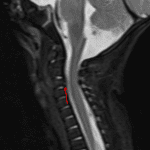

Age: 2 months

Sex: Male

Indication: Trauma, no fracture on CT

Findings

- STIR signal hyperintensity in the anterior aspect of the C3 vertebral body without associated height loss or malalignment

- Focal discontinuity of the posterior longitudinal ligament at the level of C3

- Thin anterior epidural collection at the level of C3 without significant associated narrowing of the spinal canal

- T2/STIR signal hyperintensity in the right greater than left C2-C3 facet joints

- Prevertebral soft tissue thickening extending from the craniocervical junction to the level of C4 with T2/STIR signal hyperintensity and areas of T1 signal hyperintensity

- T2/STIR signal hyperintensity in the posterior paraspinal soft tissues, most notably at the level of C2-C3

Diagnosis

- Cervical spine fracture and ligamentous injury

STIR signal hyperintensity in the anterior aspect of the C3 vertebral body concerning for acute fracture. No associated height loss or malalignment.

Thin ventral epidural hematoma at this level without significant associated spinal canal stenosis or cord signal abnormality.

Focal disruption of the posterior longitudinal ligament at the level of C3. Fluid in the right greater than left facet joints at C2-C3 raises concern for facet capsular injury. Prevertebral edema/hematoma extending from the craniocervical junction to the level of C4.